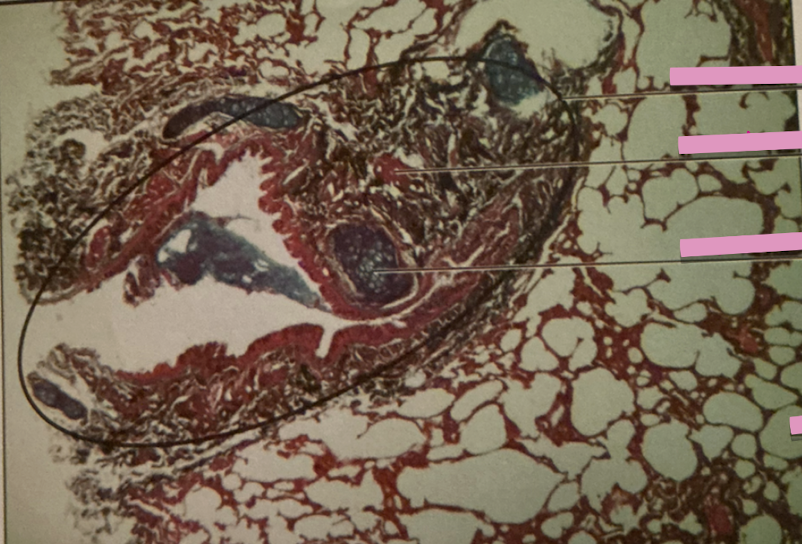

lung

lungs

flexible. fibrous bags made up of tubes & sacks

bronchioles

air passages to alveoli

alveoli

highly vascularized gas exchange compartments lined w/ simple squamous epithelium

emphysema

emphysema

breakage & collapse of alveoli —> reduction of SA fro gas exchange and O that reaches bloodstream

tuberculosis

tuberculosis

infectious, attacks lungs mainly - many asymptomatic

pneumonia

inflammatory lungs; caused by bacterial or viral infection; gas exchange w/ blood decrease; too low oxygen in blood, cellular metabolism can’t progress

pneumonia

lung carcinoma

carcinomas

primary lung cancers, from epithelial cells - very aggressive in metastasis